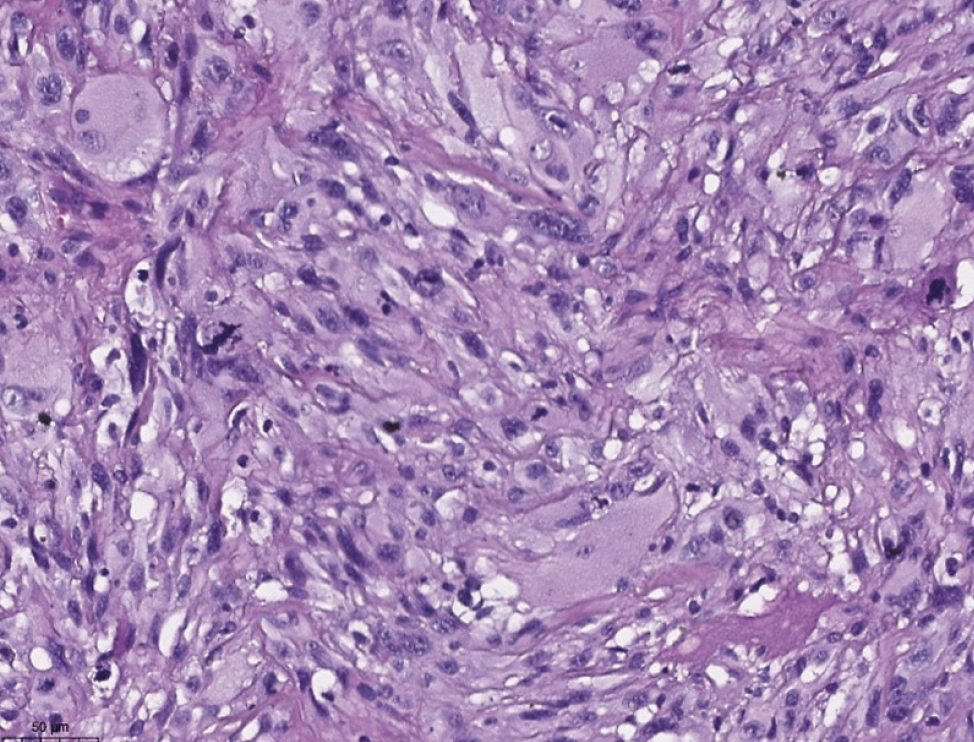

При гистологическом исследовании кожи выявлен инвазивный рост изъязвлённой полиморфноклеточной низкодифференцированной опухоли с выраженной анаплазией, участками эпителиоидно-клеточного, местами веретеновидно-клеточного строения (рис. 5, 6). Дифференциальный диагноз проводился между меланомой, фибросаркомой, атипичной фиброксантомой. Для уточнения гистогенеза проведено иммуногистохимическое исследование с использованием моноклональных антител PanCK (pan-cytokeratin), S100, MelanA, SOX10, CD34, CD10, CD68, SMA (smooth muscle antibody), desmin: экспрессии PanCK, S100, MelanA, SOX10, CD34 в опухолевых клетках не наблюдалась, в то же время отмечались диффузная выраженная экспрессия CD10, CD68 (рис. 7, 8) и позитивная экспрессия SMA, desmin в единичных опухолевых клетках.

Рис. 5. Атипичная фиброксантома (окрашивание гематоксилином и эозином, ×100).

Fig. 5. Atypical fibroxanthoma (haematoxylin and eosin staining, ×100).

Рис. 6. Атипичная фиброксантома (окрашивание гематоксилином и эозином, ×200).

Fig. 6. Atypical fibroxanthoma (haematoxylin and eosin staining, ×200).